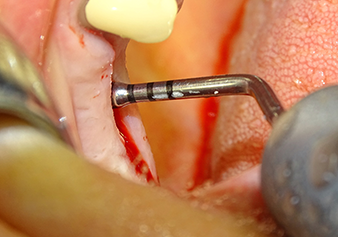

Following atraumatic preparation of the mucoperiosteal flap, the implant position was marked with the I1 instrument and the site prepared – until initial resistance was felt. Piezosurgical instruments were used in an up and down movement without any pressure being exerted. The piezoelectric vibration produced the desired and efficient cavitation.

The I2A instrument (diameter 2.0 mm) was then used to perforate the sinus floor intermittently and on the smallest scale possible. This special piezosurgical method ensures that the Schneiderian membrane is not damaged. When the Z25P was used, the membrane was already lifted slightly by the coolant supplied via the instrument tip (Fig. 3). The coolant quantity was just 50% in order to avoid high pressure in the implant bed.

The Schneiderian membrane is carefully detached with the Z25P instrument (phase 1)

Fig.3: Following marking of the implant position and initial expansion of the bed, the Schneiderian membrane is carefully detached with the Z25P instrument (phase 1).